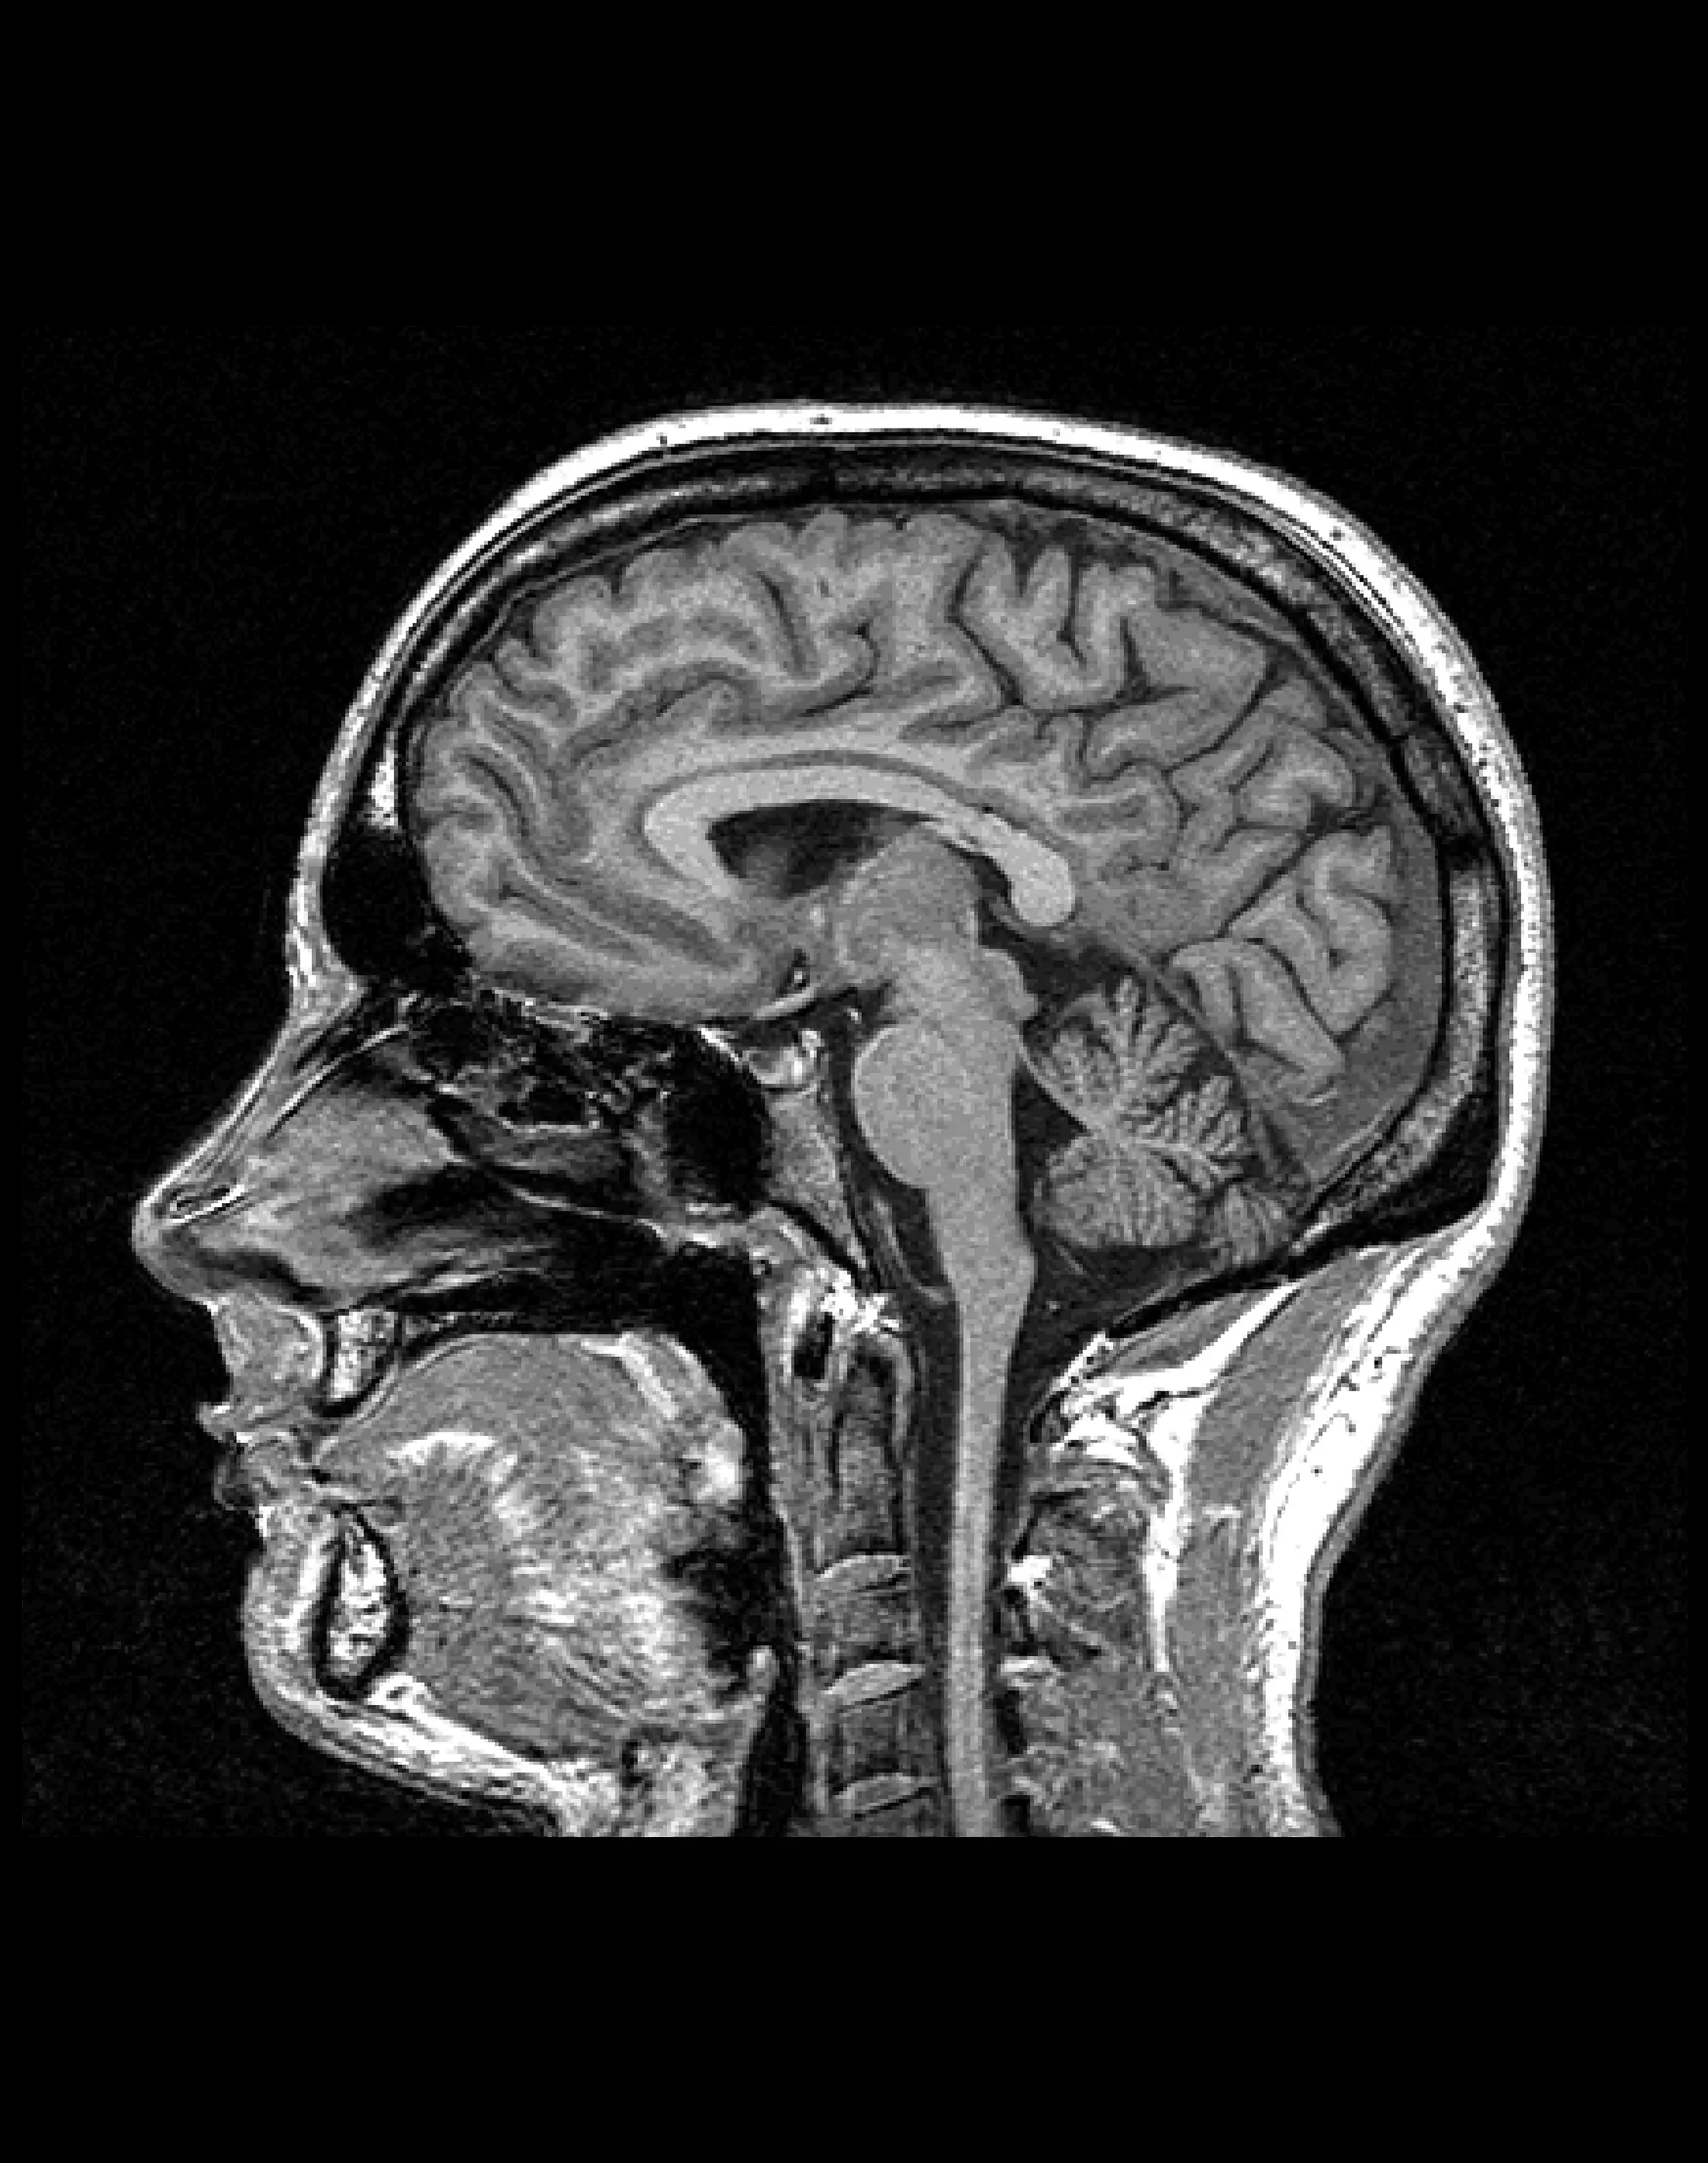

МРТ головного мозга в эпилептическом режиме

Специализированное исследование, предназначенное для выявления структурных изменений, связанных с эпилепсией.